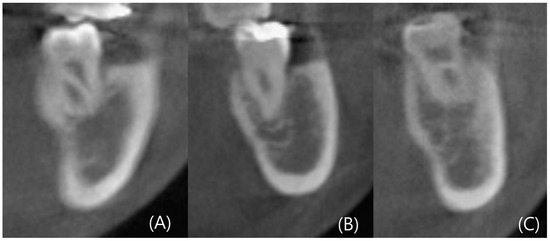

3.5. Analysis of Ridge Type Ratio